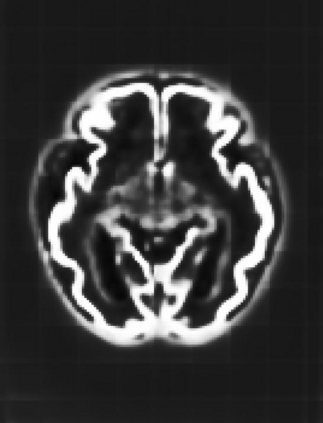

Fetal cortical plate segmentation is essential in quantitative analysis of fetal brain maturation and cortical folding. Manual segmentation of the cortical plate, or manual refinement of automatic segmentations is tedious and time-consuming. Automatic segmentation of the cortical plate, on the other hand, is challenged by the relatively low resolution of the reconstructed fetal brain MRI scans compared to the thin structure of the cortical plate, partial voluming, and the wide range of variations in the morphology of the cortical plate as the brain matures during gestation. To reduce the burden of manual refinement of segmentations, we have developed a new and powerful deep learning segmentation method. Our method exploits new deep attentive modules with mixed kernel convolutions within a fully convolutional neural network architecture that utilizes deep supervision and residual connections. We evaluated our method quantitatively based on several performance measures and expert evaluations. Results show that our method outperforms several state-of-the-art deep models for segmentation, as well as a state-of-the-art multi-atlas segmentation technique. We achieved average Dice similarity coefficient of 0.87, average Hausdorff distance of 0.96 mm, and average symmetric surface difference of 0.28 mm on reconstructed fetal brain MRI scans of fetuses scanned in the gestational age range of 16 to 39 weeks. With a computation time of less than 1 minute per fetal brain, our method can facilitate and accelerate large-scale studies on normal and altered fetal brain cortical maturation and folding.